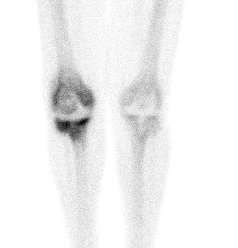

Bone Scan

Problems

- very sensitive, poor specificity

- can have increased vascularity for several months

- 1 year post cemented TKR

- 18 months post uncemented TKR

Advantage

- pathology unlikely if negative

Infection

- diffuse uptake all 3 phases (blood flow, early and delayed bone phase)

Loosening

- focal uptake unless whole prosthesis loose

- nil increase on blood flow or blood pool

Also diagnose

- stress Fractures

- RSD